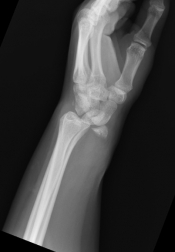

What’s the diagnosis? Gepost op 7 september 20187 september 2018 door netwerkvsseh What’s the diagnosis? @emdaily.cooperhealth.org Dit delen: Delen op X (Opent in een nieuw venster) X Share op Facebook (Opent in een nieuw venster) Facebook Delen op LinkedIn (Opent in een nieuw venster) LinkedIn E-mail een link naar een vriend (Opent in een nieuw venster) E-mail Afdrukken (Opent in een nieuw venster) Print Vind-ik-leuk Aan het laden... Gerelateerd